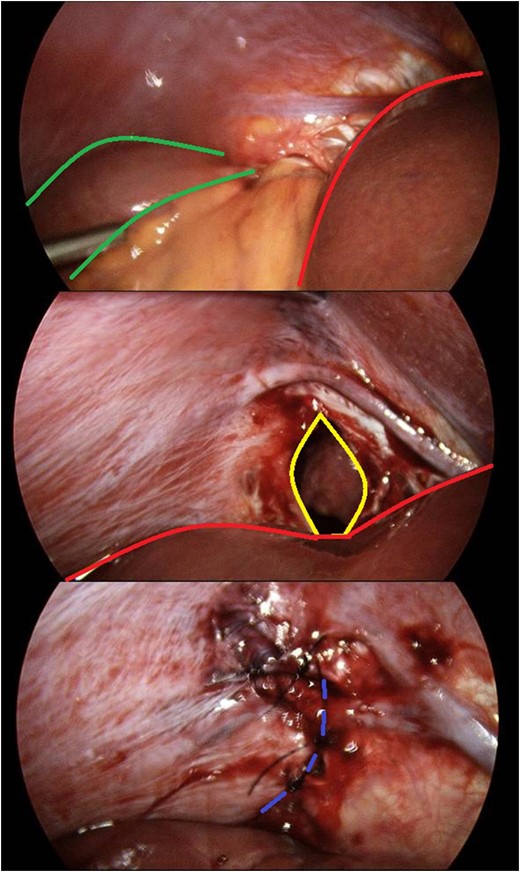

A 10 mm port was inserted infraumbilically using Hasson technique, with an additional three operating ports. Laparoscopy confirmed radiological findings of a right-sided diaphragmatic defect with herniation of terminal ileum.

There was evidence of small bowel obstruction, with distended small bowel loops and constriction at the defect. The defect’s location did not appear consistent with a congenital hernia. The hernia was reduced by gentle traction and the defect was closed laparoscopically with interrupted 0-monosof sutures. The entire small bowel was viable and intact (Fig. 3).

Identification and laparoscopic reduction of diaphragmatic hernia in sequence. Green borders outline small bowel; red borders delineates hepatic edge; yellow margins signifies diaphragmatic defect; and purple hashed line is closed defect.